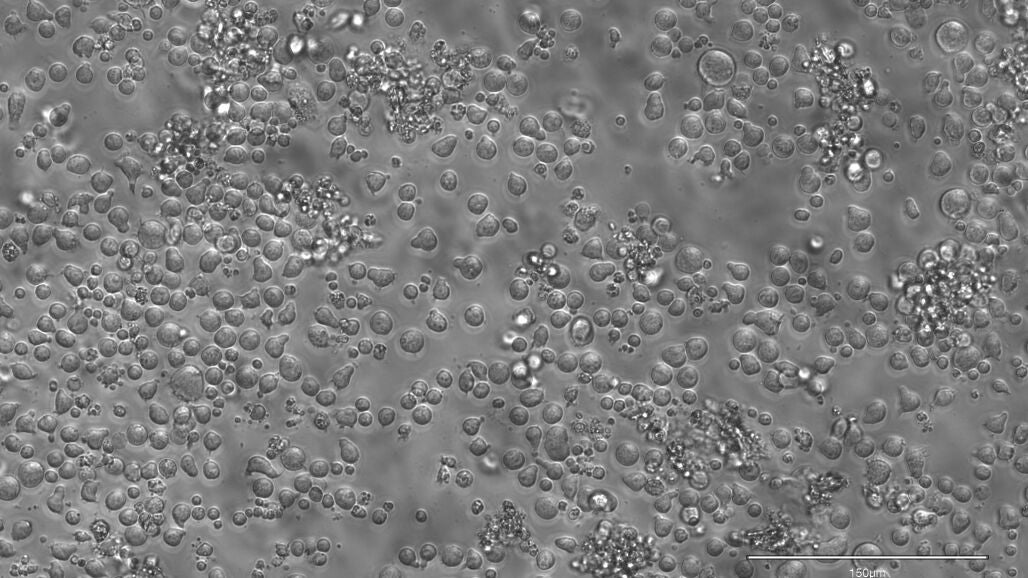

Para ello, los investigadores desarrollaron EPI-Clone, una técnica gracias a la cual es posible leer estos códigos de barras de metilación en cada una de las células y de esta manera pudieron generar mapas que revelan información acerca de qué células madre se expanden y, por lo tanto, contribuyen a la sangre y cuáles se extinguen a lo largo del tiempo.

Gracias a ello, los investigadores pudieron observar que en la sangre de las personas jóvenes hay una gran cantidad de células madres diferentes, las cuales producen un conjunto diverso y variado de células, mientras que a edad avanzada, principalmente a partir de los 50 años, unas pocas se imponen a sus vecinas, tomando gradualmente el control de la producción de sangre. A partir de los 60 años de edad, este fenómeno es aún más evidente y pronunciado.